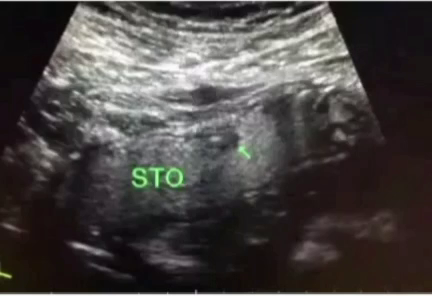

胃肠超声显示,胃窦部胃壁增厚,

图像层次感很清晰!